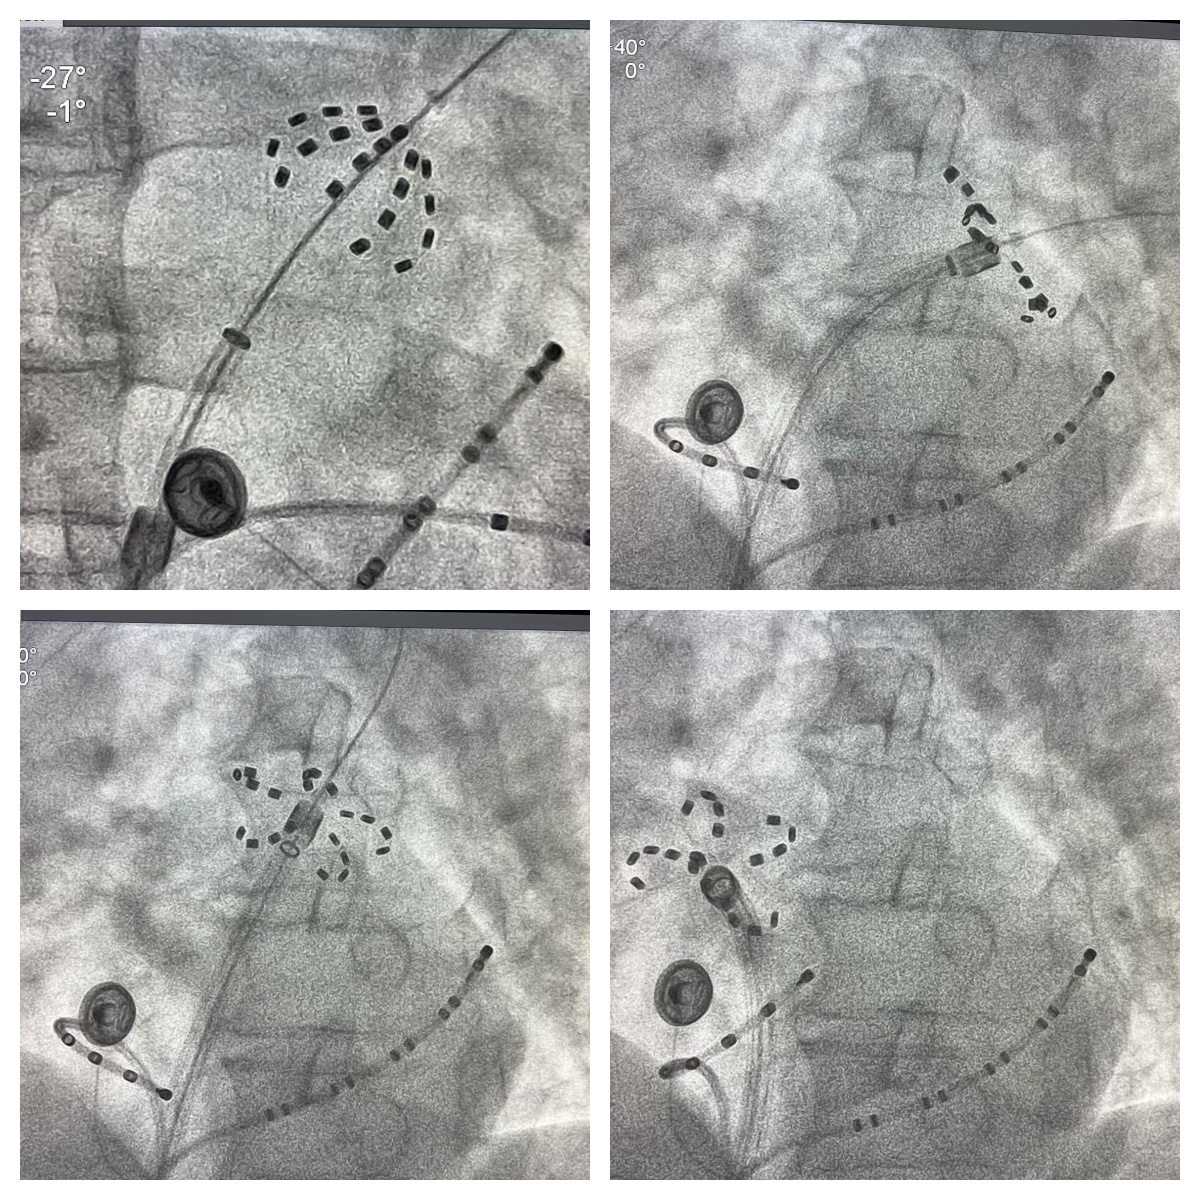

手术过程

经过详细的个体化评估,谢鸿发教授与李海鹰教授决定为患者采用最新一代波科 FaraPulse 脉冲消融系统进行手术。此脉冲消融系统在国外及香港已常规开展,且已完成上万例消融手术,谢鸿发教授积累了极为丰富的经验。谢鸿发教授和李海鹰教授运用 Farawave 导管,在房颤状态下开启双侧肺静脉隔离,发放脉冲数秒后,肺静脉电位消失,房颤即刻转为窦性心律,随后检验双侧肺静脉双向传导阻滞,手术取得圆满成功。双侧肺静脉隔离时间约为 30 分钟。